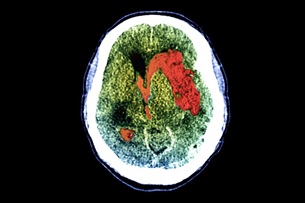

Máu (màu đỏ; nhuộm màu nhân tạo) tụ lại trong não của người bị đột quỵ, một nguyên nhân phổ biến gây hôn mê (ảnh: Zephyr/Science Photo Library).